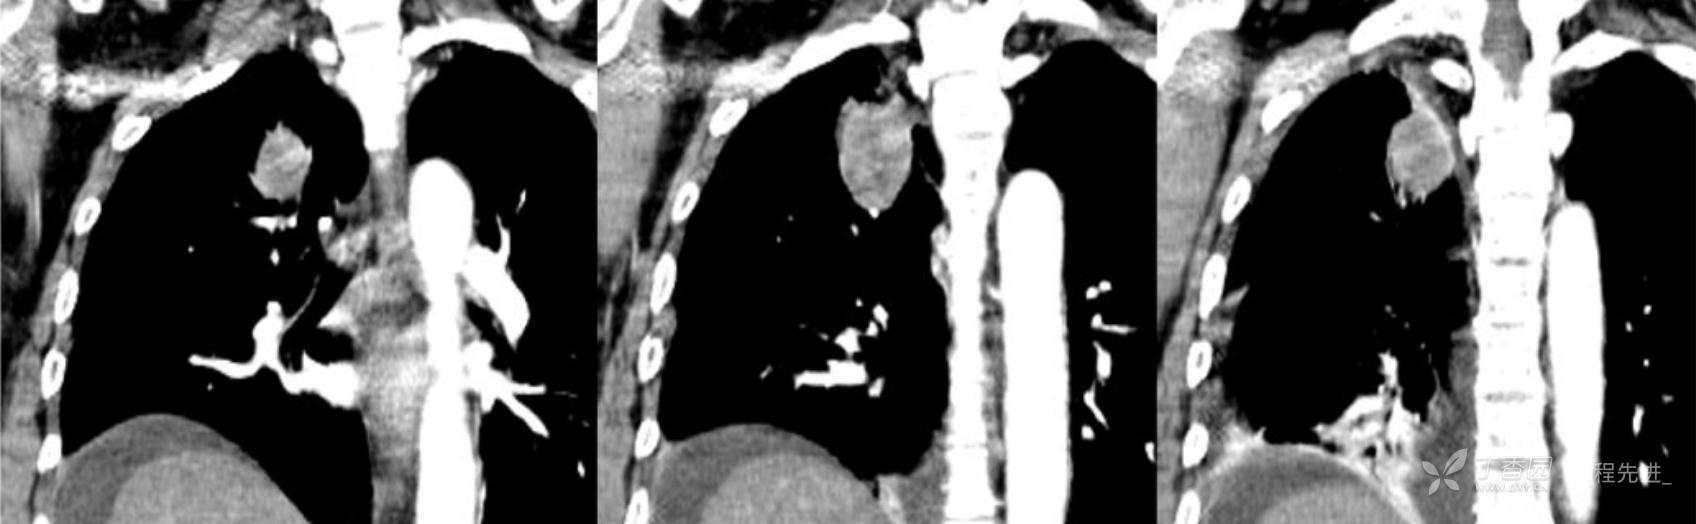

简要病史:乏力、纳差20余天,皮肤巩膜黄染半月偶有咳嗽,咳白痰,全身皮肤巩膜黄染。无咯血,无明显胸闷、胸痛,无明显气促,无发热及盗汗。精神欠佳,纳差,睡眠一般,二便正常